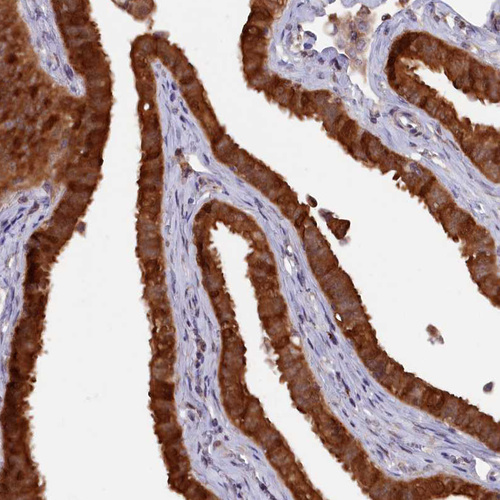

Immunohistochemical staining of human Fallopian tube shows strong cytoplasmic positivity in glandular cells.